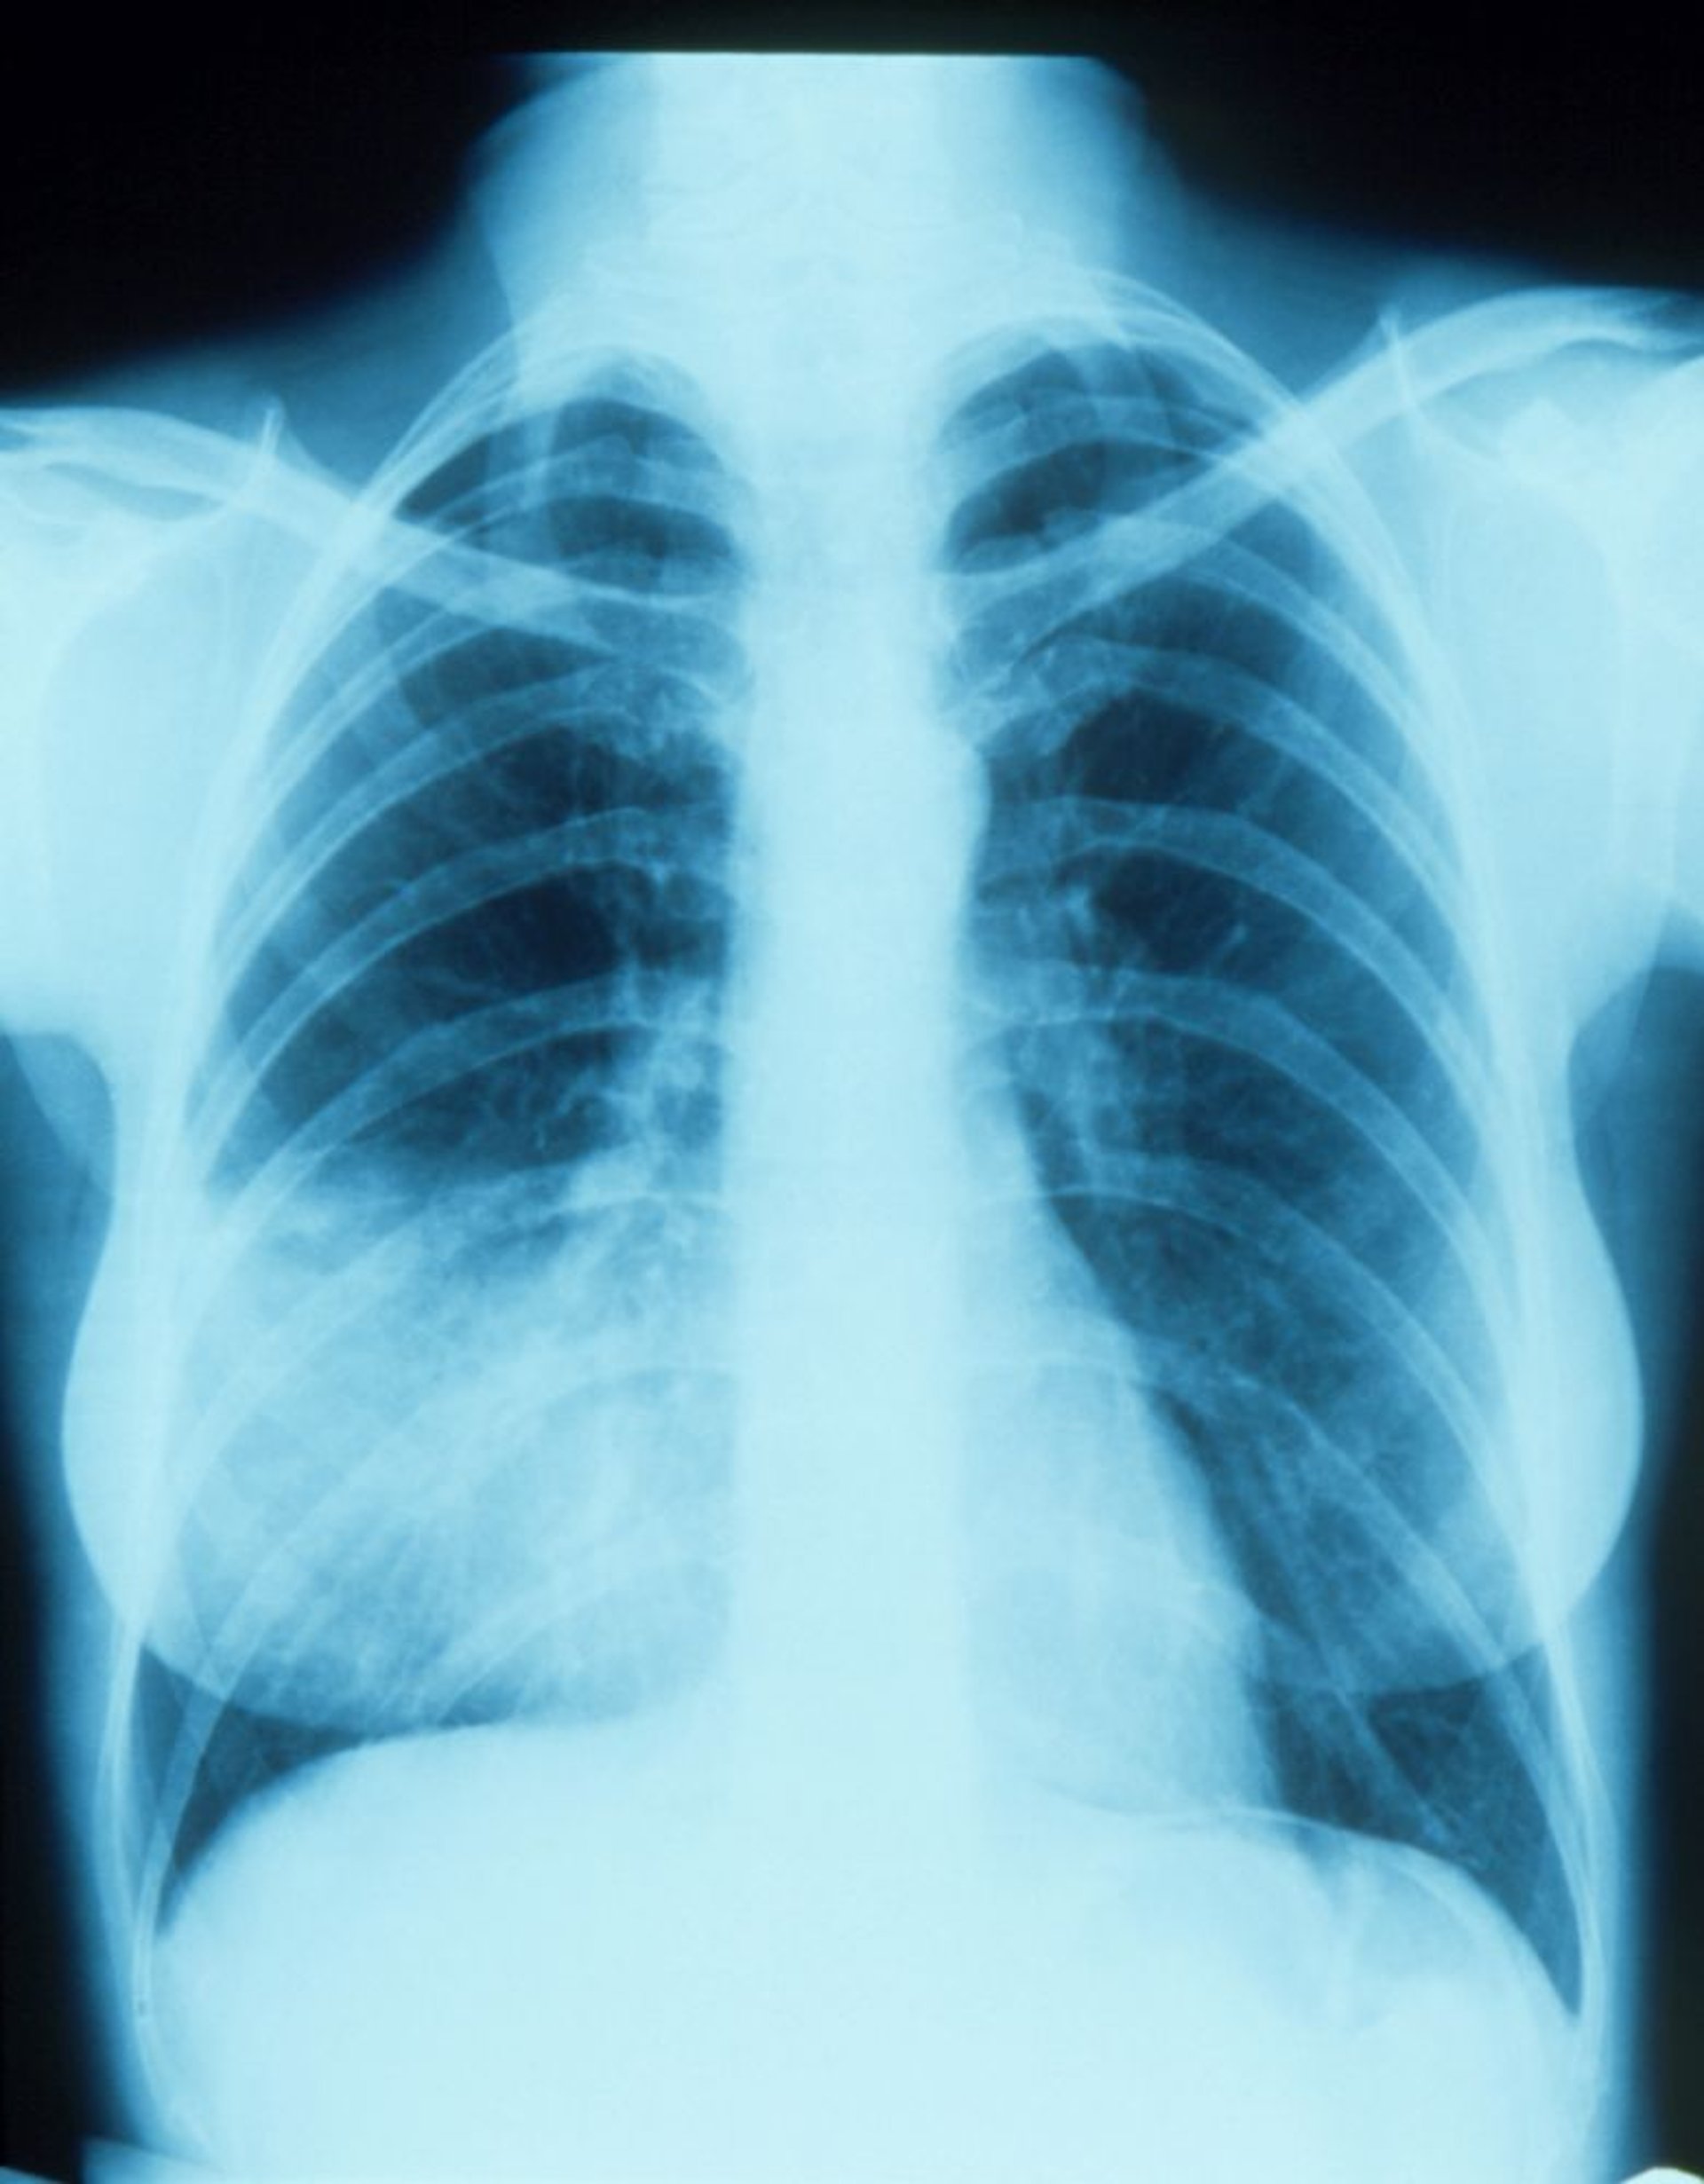

Pneumonia do lobo direito médio com sinal da silhueta

Essa radiografia do tórax mostra um infiltrado que parece se mesclar com a borda cardíaca direita (sinal da silhueta). O sinal da silhueta indica posicionamento contíguo das 2 estruturas com radiodensidades semelhantes; a parte do pulmão contígua com a borda direita do coração é o lobo médio direito, de modo que é a parte que apresenta infiltrado e pneumonia.